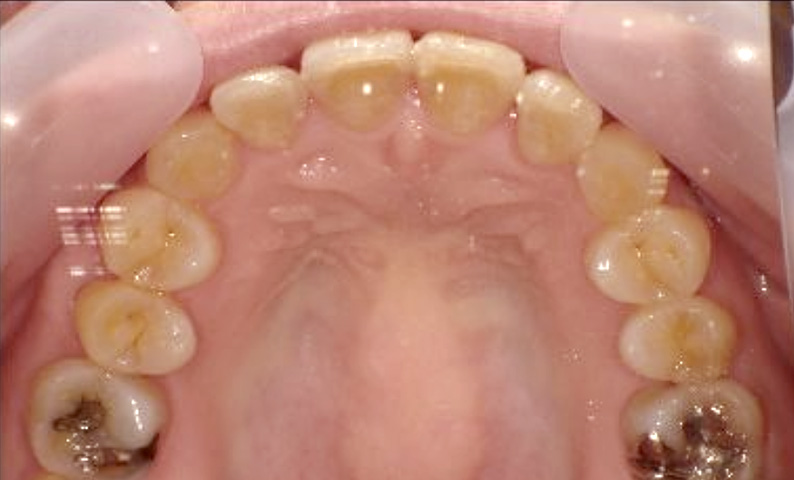

症例_003 下顎だけの部分矯正

治療期間:10ヶ月金額:24万円+税女性前歯のガタガタ下の前歯だけ上顎は補綴治療中

| Before | After |